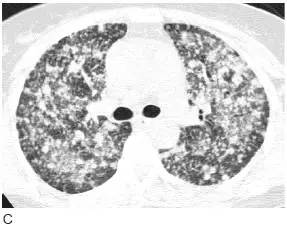

图9 弥漫性细支气管肺泡癌(BAC)

A. 伴双肺实变的BAC;

B. 伴两肺模糊小结节;

C. 同一患者高分辨率CT 显示弥漫分布的小结节